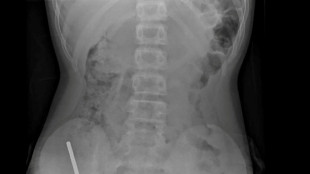

"The king underwent precautionary and thorough medical exams in a context of Covid and after the sudden death of his close advisor."